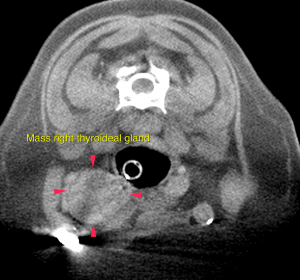

A well-defined, ovoid mass lesion with lobulated appearance and undulating surface is seen in the area of the right parotid salivary gland, measuring 3.8 x 3 x 3.5 cm in size. After contrast administration the mass lesion presents moderate irregular contrast enhancement with multiple spherical non-contrast enhancing areas. The right superficial cervical lymph node is prominent and presents a moderate increased short-to-long-axis ratio of 0.5. The right thyroid gland presents severe enlargement at 2.4 x 2.4 x 2.8 cm. The regular parenchyma is completely displaced by ill-defined moderately contrast enhancing tissue with multiple spherical non-contrast enhancing areas. At the level of the neck the tracheal rings are mildly flattened and the luminal diameter is reduced.